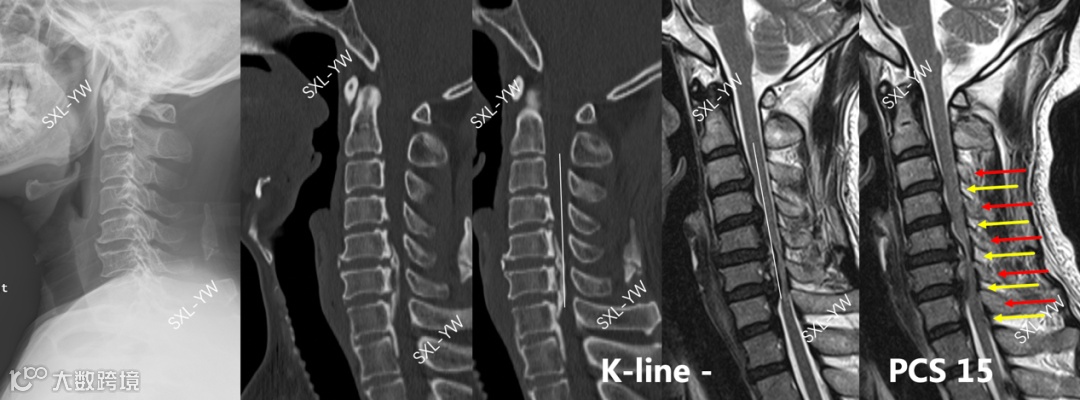

日本学者Fujiyoshi等[4]于2008年提出K线的概念,将C2与C7椎管中点的连线定义为K线,如果骨化物超过K线定义为K线阴性,作者认为K线阴性的OPLL患者单开门术后脊髓漂移将不充分、神经功能恢复将不理想。作者认为颈椎曲度、骨化占位率会明显影响脊髓漂移程度、神经功能恢复情况,K线将这2个指标整合成1个指标,是重大的临床发现。

K线对单开门手术的预测作用有2部分组成:① K线阴性OPLL患者单开门术后脊髓漂移将不充分,这是预测脊髓漂移情况;② 脊髓漂移不充分就会导致神经功能恢复不理想,这是预测神经功能恢复情况。K线一经提出就得到众多学者的支持、推崇,K线阴性的OPLL被认为是单开门手术的禁忌,此类患者需要行前路减压融合术或后路椎板切除矫形内固定术[5]。

图2 K线的定义及其在单开门手术中指导意义

我们对大量的临床病例进行总结,发现K线存在诸多不足:K线仅适用于OPLL,且对OPLL累及上颈椎、上胸椎不适用;过于强调颈椎曲度在单开门手术中的作用;只承认单开门手术的间接减压作用,完全忽略了单开门手术的直接减压作用;认为脊髓漂移不充分就会导致神经功能将恢复不理想,二者存在必然的联系。

我们大量的临床病例证实:K线阴性的OPLL患者单开门术后脊髓漂移充分、神经功能恢复良好[7]。因此,我们认为:K线不具有预测脊髓漂移程度和神经功能恢复的作用。

图5 K线阴性的OPLL患者单开门术后脊髓漂移充分、神经功能恢复良好